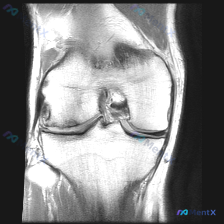

今天遇到一个挺典型的临床情况,整理出来和大家聊聊:核心问题是临床观察提示「软骨异常」,但我们拿到的单幅膝关节MRI冠状位T2加权像分析却全是阴性结果,一起来理理思路。 先给大家放完整影像信息: 1. 整体结构对位:股骨远端胫骨近端对位正常,无骨折错位 2. 骨髓信号:股骨髁、胫骨平台骨髓信号大致均匀...

刚梳理完一份膝关节MRI读片病例,核心问题是「这张图像中可视觉识别的潜在异常是什么?」,标准答案提示是软骨异常,不过整理完发现这个病例其实挺值得讨论,分享一下完整分析思路。 病例影像基础信息 这是一张膝关节MRI冠状位影像,我们先整理客观观察到的所有征象: 1. 骨骼结构:股骨远端、胫骨平台骨皮质连...